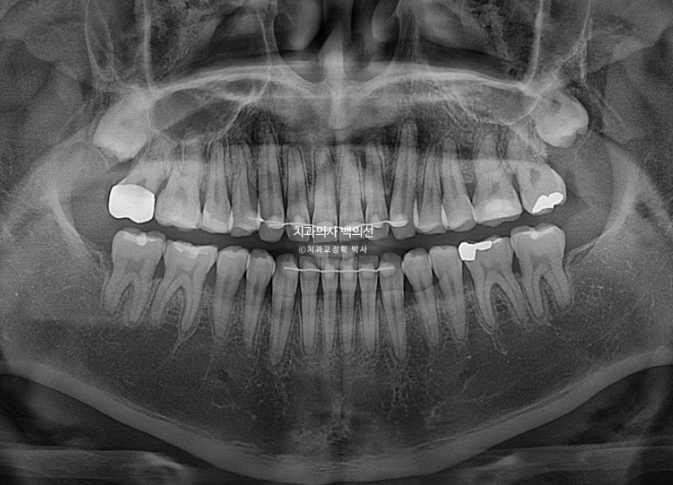

25.04

치근흡수는 없고 치근평행도는 좋습니다.

앞니 반대교합이 아래턱을 더 내밀어 물게 하는 경우가 있습니다.

이런 경우 교정만으로 턱이 제 위치를 찾으면서 디로 약간 들어가게 됩니다.

엑스레이 중첩에서 확인이 되듯이 말입니다.